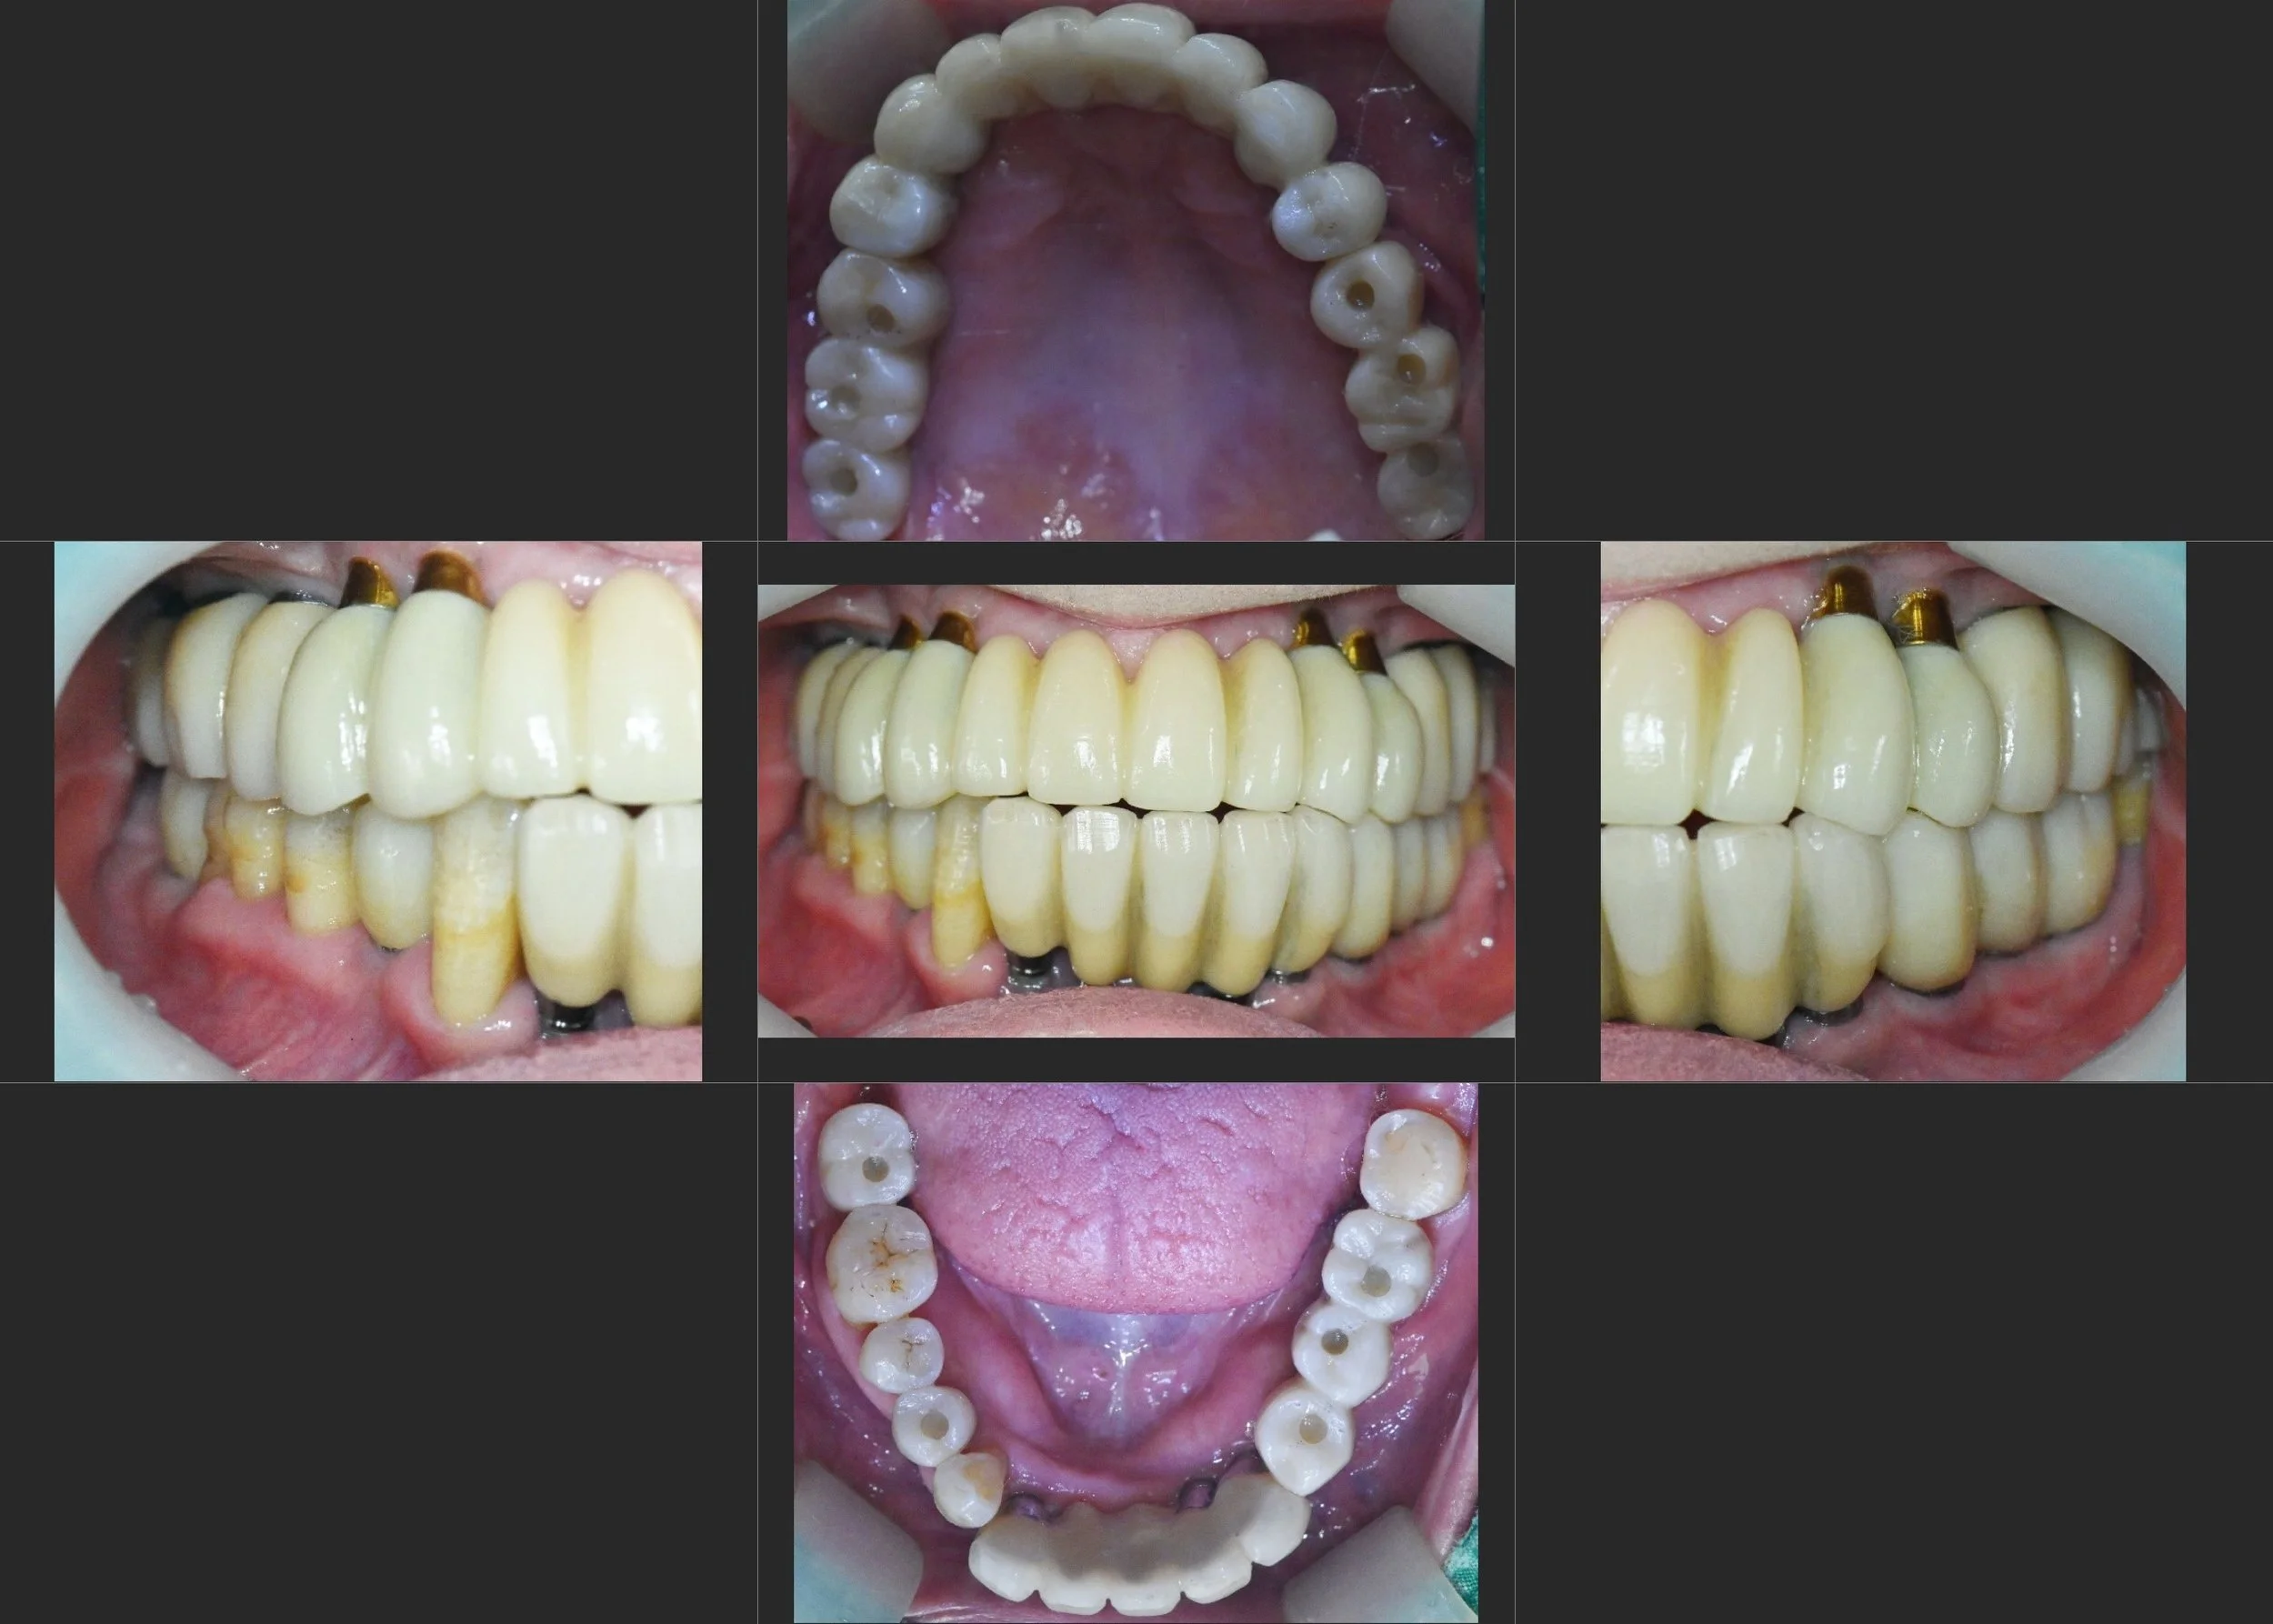

INTRA ORAL - AFTER